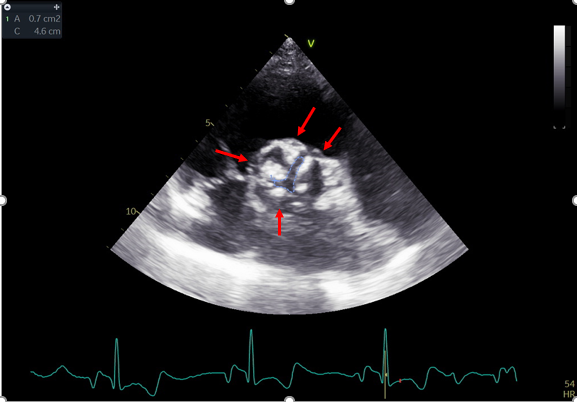

Campania: primo impianto TAVI in Italia con nuova tecnologia per la stenosi aortica

A Castel Volturno il primo impianto italiano di TAVI con nuovo sistema di rilasc...